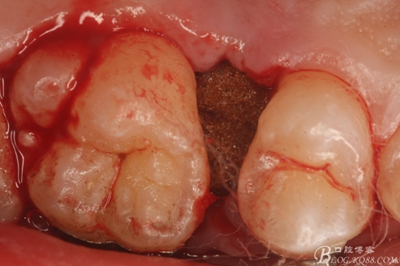

圖10.去除牙齦組織后。露出15牙根斷面,合面無法脫位